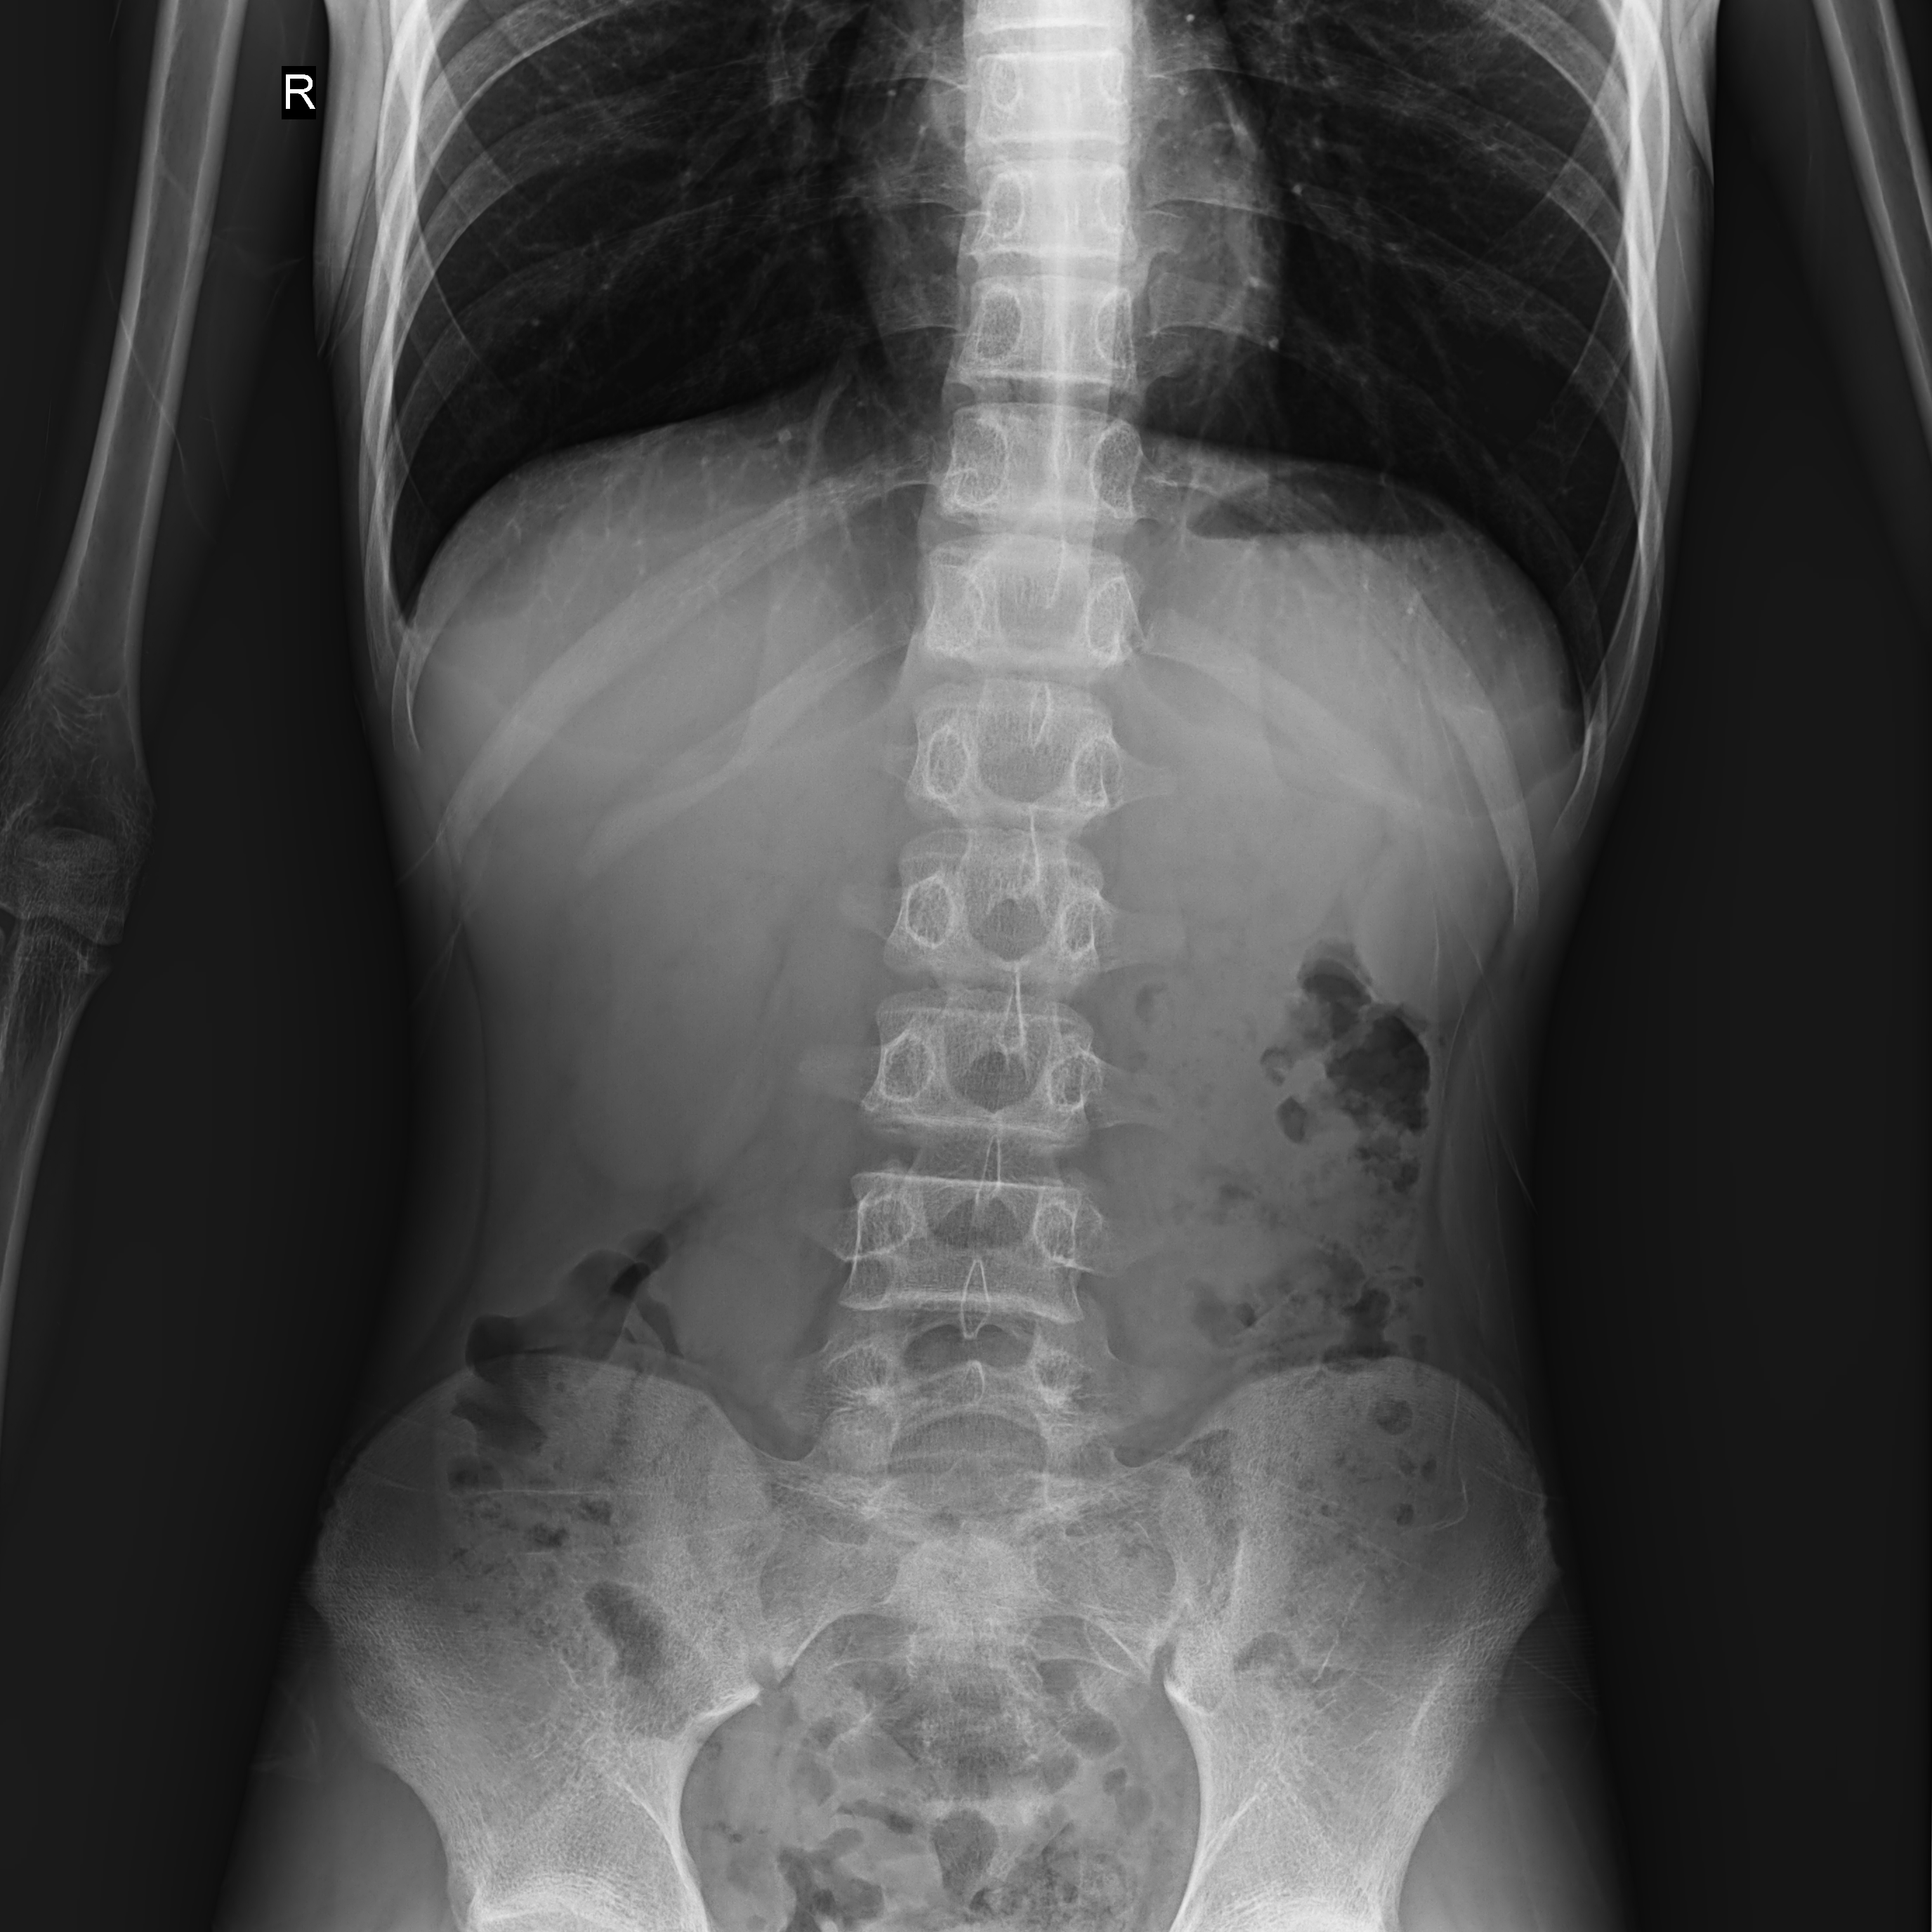

普利德醫(yī)療自主研發(fā)的新一代數(shù)字化X線透視攝影系統(tǒng),可應用于DR攝影、數(shù)字透視、數(shù)字造影以及可視化精準DR拍片等多種臨床X線檢查領域。

● 最高幀速可達30幀/秒,動態(tài)采集清晰流暢,避免漏診、誤診情況的發(fā)生;

● 在可視過程或回放過程中,如發(fā)現(xiàn)疑似病灶,可進行毫秒級高清點片,隨時抓取單幀圖像,精準捕抓病灶。